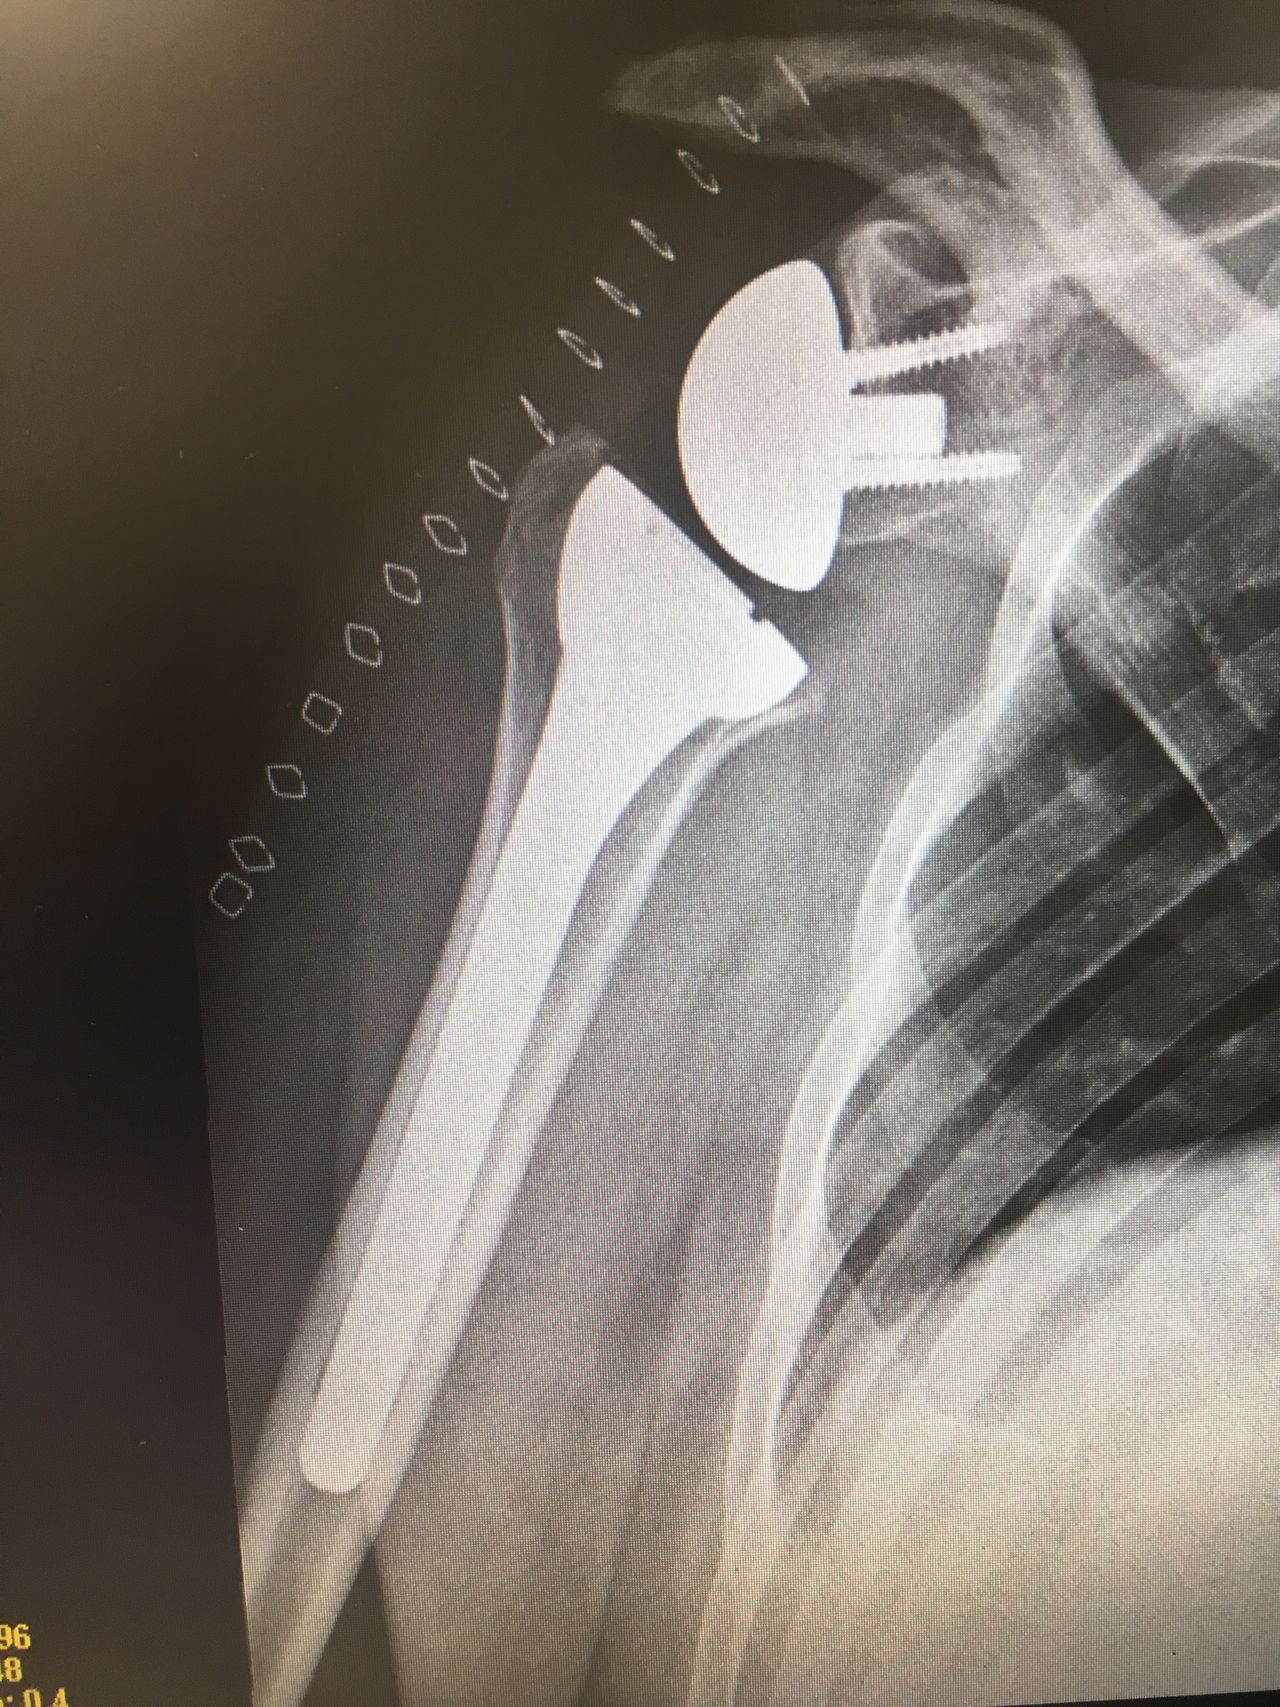

Fotos y vídeos

Actualizacion 29.11. Dia 3.11.me realizó una artroplastia y osteotomia de hombro en la Clínica Sagrada familia,atención en la Clínica muy buena, y hoy ,1 mes después de la operación puedo decir que la recuperacion va muy bien,evidentemente en las operaciones de éste tipo hay k tener paciencia.Seguimiento postoperatorio muy correcto,trato excelente y cercano en cada visita.• Centre Medic Martorell • Otro •